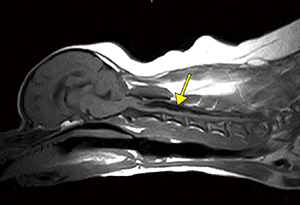

■症例1:イヌ,頸椎ヘルニア

膝コイル,T2WI,SAG,FOV:250mm,

TR/TE:2500/120,スライス厚:3mm,

マトリックス:288×224,scan time:5:48